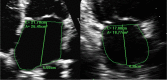

Methods: All patients underwent echocardiography preablation, 3 and 12 months post-ablation. LA structure and function were assessed by 2-dimensional volume and speckle tracking strain measurements of LA reservoir, conduit, and contractile strain. Left ventricular diastolic function was measured using transmitral Doppler filling velocities and myocardial tissue Doppler velocities to derive the e', E/e', and E/A ratios. Continuous rhythm monitoring was achieved using an implantable loop recorder.

Results: Eighty-three patients had echocardiographic data suitable for analysis. Their mean age was 63.6±9.7 years, 73.5% were male, had AF for 22.8±11.6 months, and had a mean LA maximum volume of 48.8±13.8 mL/m2. Thirty patients maintained sinus rhythm, and 53 developed AF recurrence. Ablation led to similar reductions in LA volumes at follow-up in both rhythm groups. However, higher LA emptying fraction (36.3±10.6% versus 27.9±9.9%; P<0.001), reservoir strain (22.6±8.5% versus 16.7±5.7%; P=0.001), and contractile strain (9.2±3.4% versus 5.6±2.5%; P<0.001) were noted in the sinus rhythm compared with AF recurrence group following ablation at 3 months. Diastolic function was better in the sinus rhythm compared with the AF recurrence group with an E/A ratio of 1.5±0.5 versus 2.2±1.2 (P<0.001) and left ventricular E/e' ratio of 8.0±2.1 versus 10.3±4.1 (P<0.001), respectively. LA contractile strain at 3 months was the only independent predictor of AF recurrence.